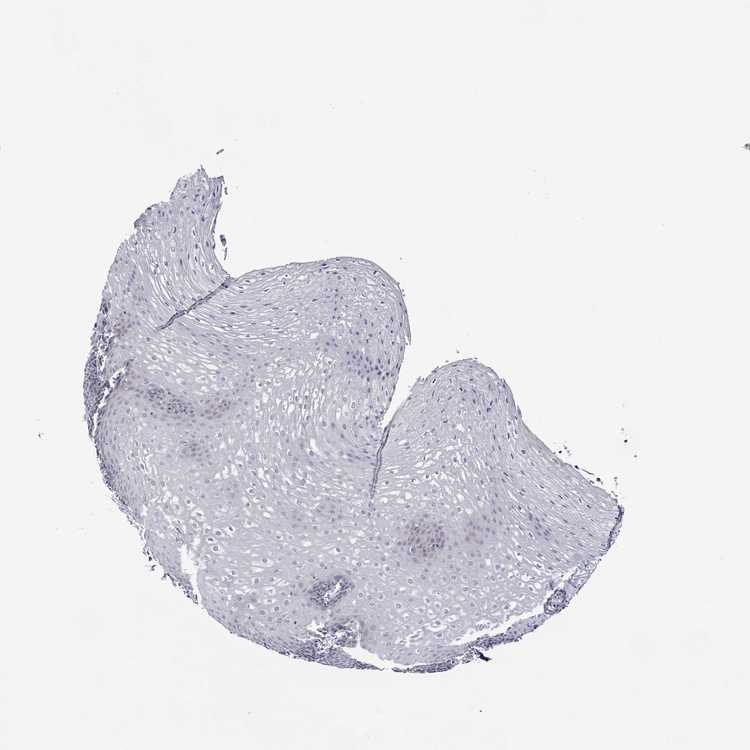

ESOPHAGUS - Antibody stainingi

Antibody staining in the annotated cell types in the current human tissue is reported as not detected, low, medium, or high, based on conventional immunohistochemistry profiling in selected tissues. This score is based on the combination of the staining intensity and fraction of stained cells.

Each image is clickable and will lead to virtual microscopy that enables deeper exploration of all samples and also displays staining intensity scores, fraction scores and subcellular localization as well as patient and tissue information for each sample.

Antibody HPA045724

Squamous epithelial cells Not detected